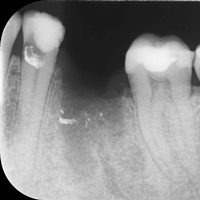

Wybielanie obejmujące pojedyncze zęby jest dość często spotykane. Najczęstszą przyczyną dyskoloracji zęba jest obumarcie miazgi i brak następowego poprawnego leczenia kanałowego, lub leczenie nieprawidłowe. Czasami udaje się przeprowadzić proces wybielania, który jest zadowalający dla pacjenta, a czasami w oparciu o uzyskany wynik można przeprowadzić leczenie protetyczne np. koroną lub licówką całoceramiczną.

Trzeba jednak uważać, ponieważ nieumiejętnie przeprowadzone wybielanie może być przyczyną resorpcji wewnętrznej i może sie skończyć utratą całego zęba...juz wybielonego. Poniżej zdjęcia przed i po leczeniu mikrochirurgicznym resorpcji.